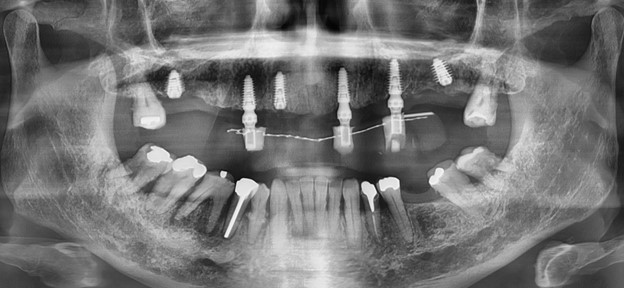

Xray show many infection around upper teeth

Radiograph after surgery 1 day

Radiograph after loading final prosthetic